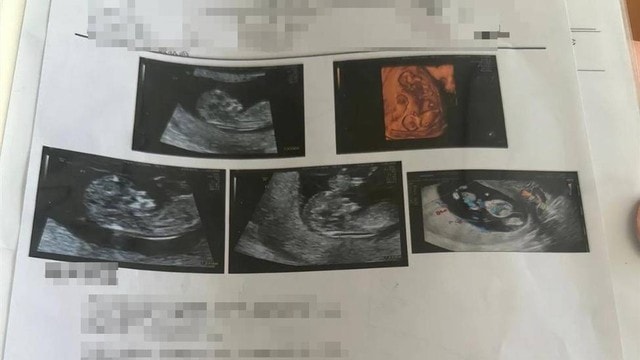

Mới đây, cô Wang đến từ Phúc Thuận, tỉnh Liêu Ninh, Trung Quốc, đã đăng tải trên mạng xã hội rằng cô đang mang thai 16 tuần. Từ tháng 11 đến tháng 12/2025, cô đã trải qua 4 lần khám thai tại bệnh viện và mỗi lần siêu âm đều cho thấy có thêm một thai nhi, dẫn đến việc mang thai 4.

Theo lời Wang, cô 30 tuổi và mang thai tự nhiên vào tháng 9/2025. Wang đã đi khám thai 3 lần tại Bệnh viện Sản Nhi Phúc Thuận vào tháng 11/2025. Lần khám đầu tiên cho thấy cô mang thai đơn, lần thứ 2 cho thấy mang thai đôi và lần thứ 3 cho thấy mang thai ba. Để làm rõ tình hình, Wang đã đến Bệnh viện Sản Nhi Thẩm Dương để khám lại vào tháng 12/2025 và kết quả siêu âm cho thấy cô mang thai 4.

Theo kết quả siêu âm thai lần thứ 4 của Wang, thai nhi thứ 4 của cô được phát hiện là không có tim. Bác sĩ giải thích rằng mặc dù thai nhi thứ 4 của cô không có tim thai nhưng mạch máu lại nối với 3 thai nhi còn lại, được các thai nhi khác cung cấp máu. Nếu cả 4 thai nhi cùng trứng phát triển bình thường, có thể dẫn đến các thai nhi khác có triệu chứng suy tim bẩm sinh.